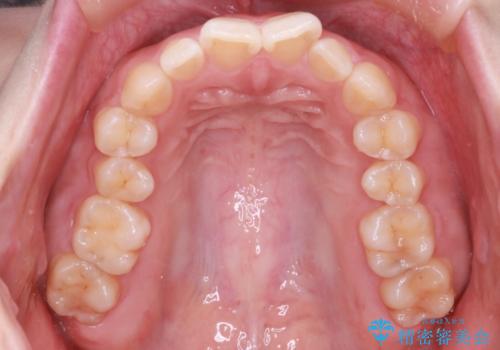

【インビザライン】前歯が出てるのを治したい

- 前歯の凸凹と前突を主訴に来院されました。

インビザラインにて治療をおこない、歯並びを改善することができました。